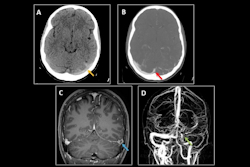

The incidence of ischemic stroke among adolescents and young adults is now a public health concern due to significant morbidity and extended disability in this age group. How can imaging help? A team from Santander in Spain has provided some answers.